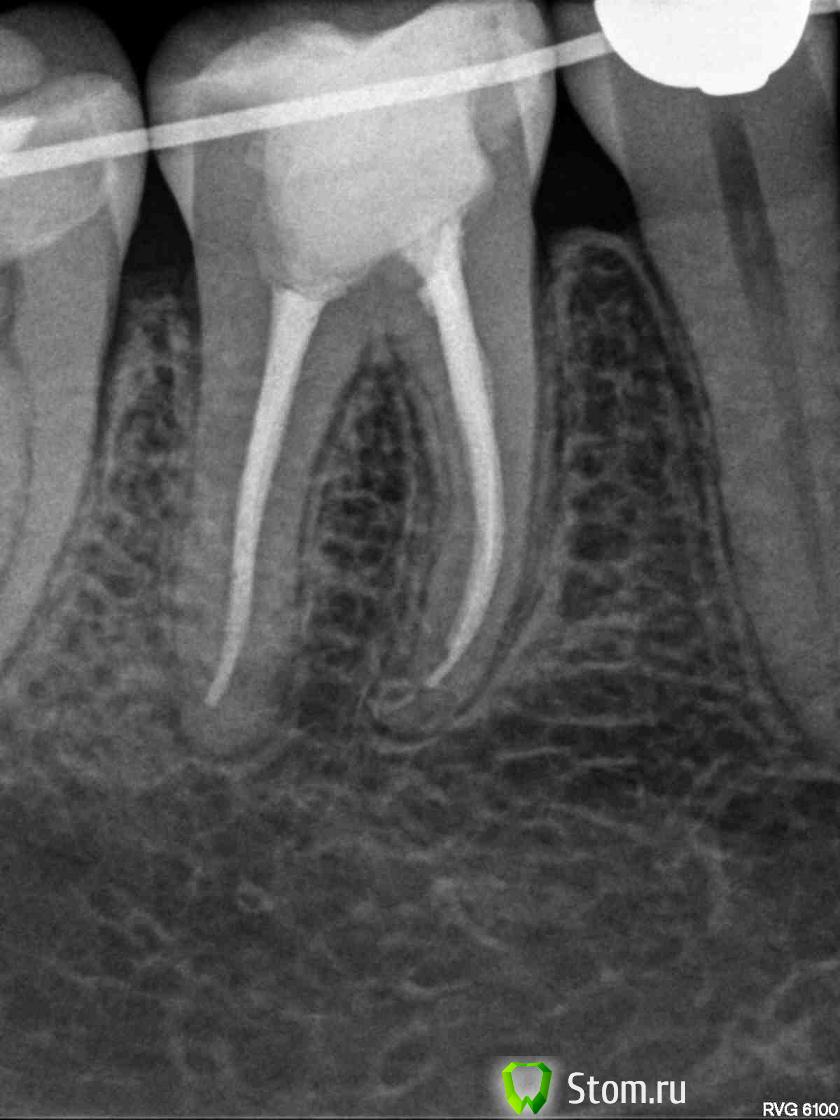

ger_berra Опубликовано 11 февраля, 2012 Поделиться Опубликовано 11 февраля, 2012 Как ощущения?По снимкам гуд! Ссылка на комментарий

Anna_M Опубликовано 11 февраля, 2012 Автор Поделиться Опубликовано 11 февраля, 2012 Как ощущения? Спасибо, все хорошо! По снимкам гуд! Екатерина, Вы меня очень сильно обрадовали тем, что на снимках Вам все нравится! Спасибо! Ссылка на комментарий